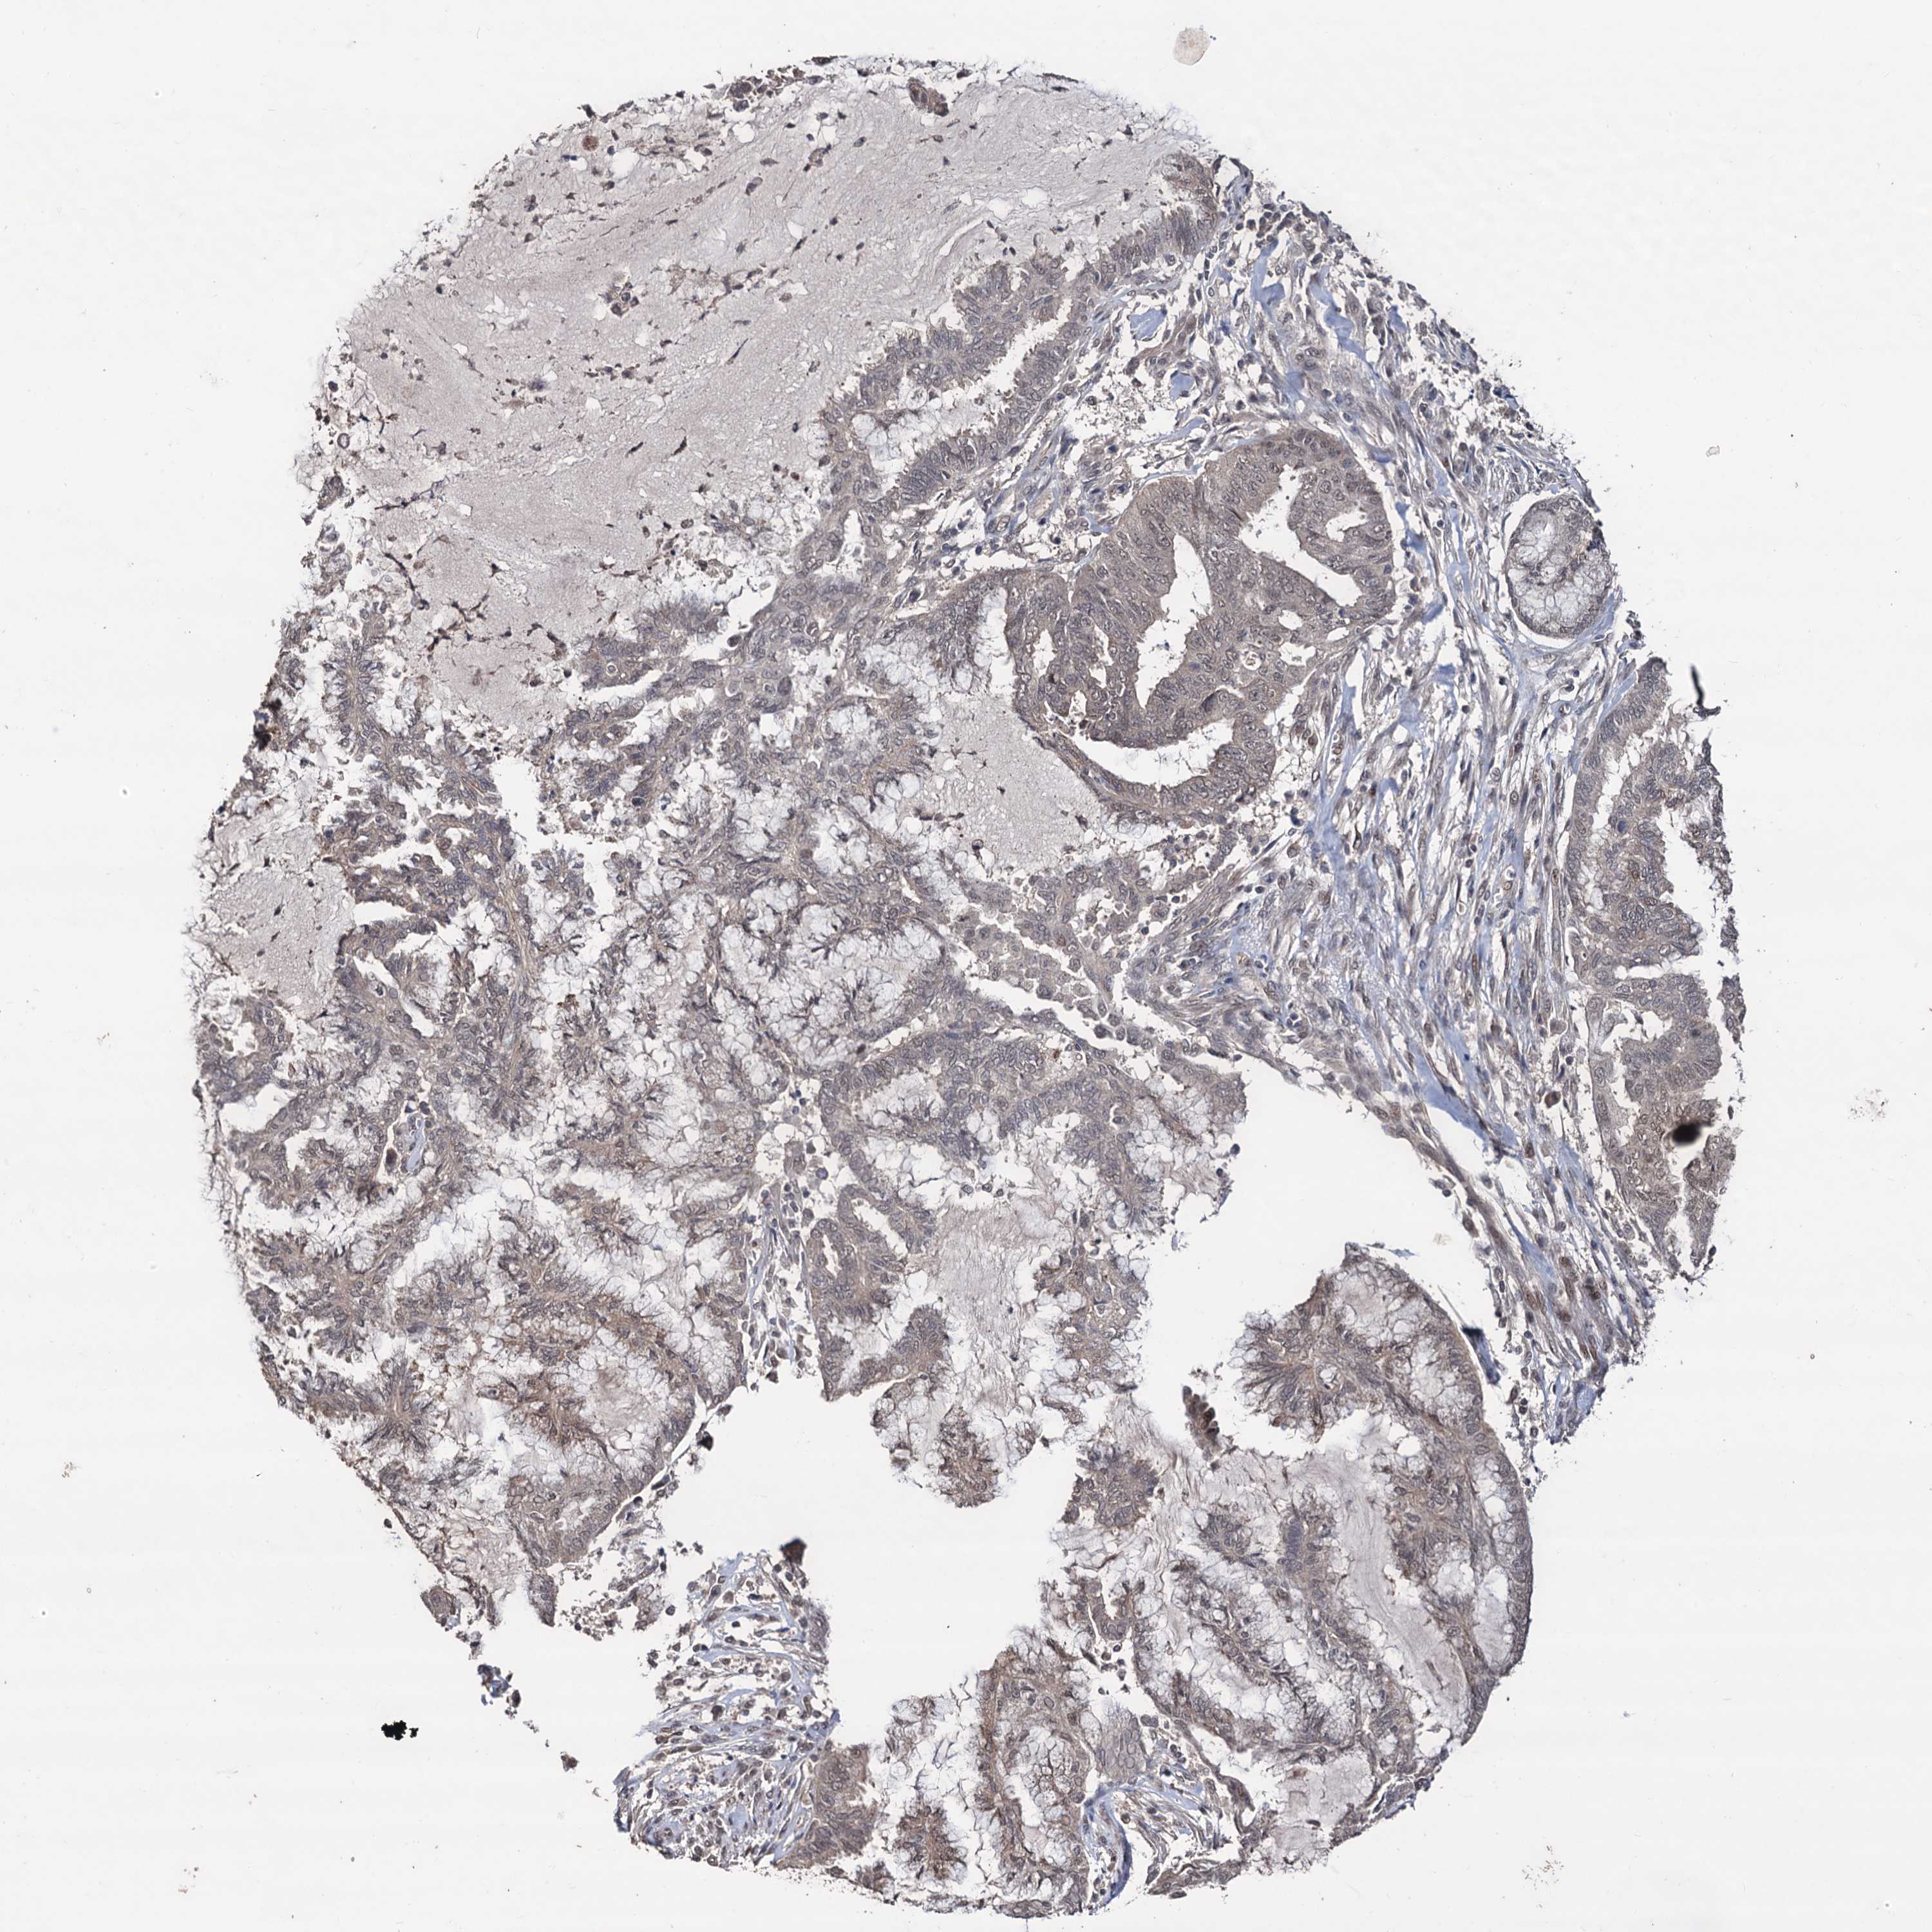

ENDOMETRIAL CANCER - Protein expressioni

A mouse-over function shows sample information and annotation data. Click on an image to view it in a full screen mode. Samples can be filtered based on level of antibody staining by selecting one or several of the following categories: high, medium, low and not detected. The assay and annotation is described here.

Note that samples used for immunohistochemistry by the Human Protein Atlas do not correspond to samples in the TCGA dataset.

Antibody stainingi

Antibody staining in the annotated cell types in the current human tissue is reported as not detected, low, medium, or high, based on conventional immunohistochemistry profiling in selected tissues. This score is based on the combination of the staining intensity and fraction of stained cells.

Each image is clickable and will lead to virtual microscopy that enables deeper exploration of all samples and also displays staining intensity scores, fraction scores and subcellular localization as well as patient and tissue information for each sample.

Antibody HPA040398

Staining

High

Medium

Low

Not detected

Intensity

Strong

Moderate

Weak

Negative

Quantity

>75%

75%-25%

<25%

None

Location

Nuclear

Cytoplasmic/membranous

Cytoplasmic/membranous,nuclear

Adenocarcinoma, NOS

Adenocarcinoma, metastatic, NOS